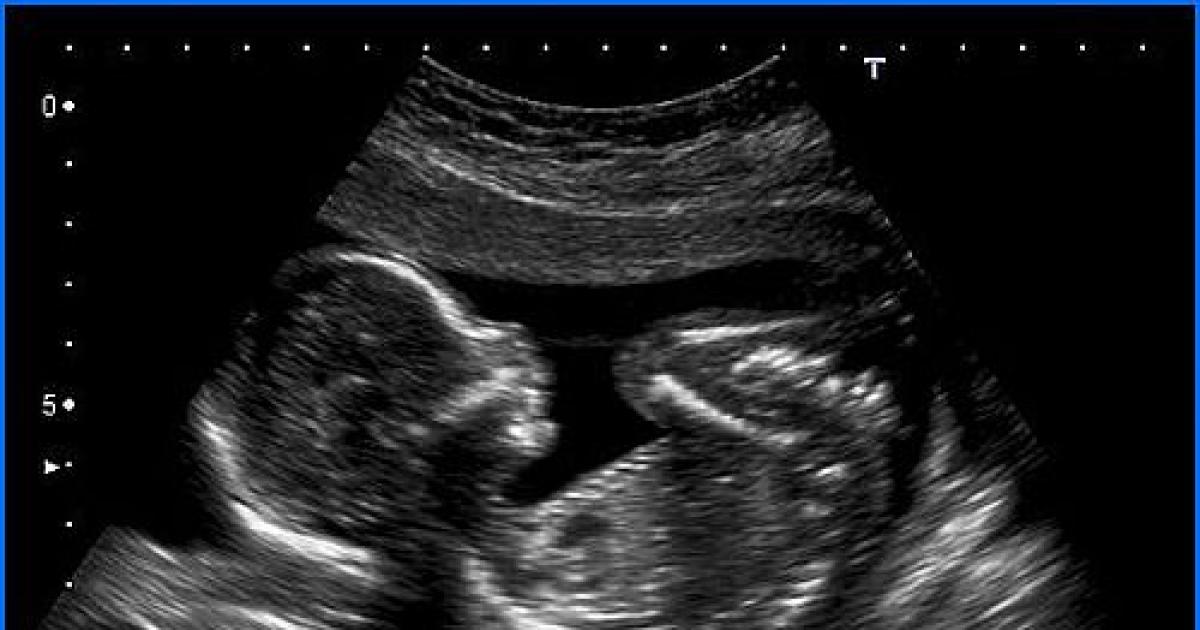

The doctors said in their report that there was a "complete absence of brain and skull" of the foetus and survival rate was minimal.

The apex court's order came on a plea of a woman seeking its nod to undergo medical termination of pregnancy on the ground that the skull of the foetus had not formed and the child, if born alive, may not be able to survive.